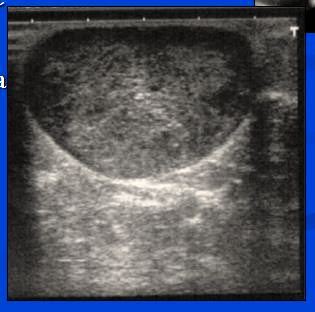

- UZ - ´polycyklická poměrně ohraničená rezistence 4x4cm, v Doppler.zobrazení výrazně vaskularizované´

- UZ – vlevo uzlovitá heterogenní struktura žlázy s anechogenními tekutinovými porcemi, v axile bez lymfadenopatie